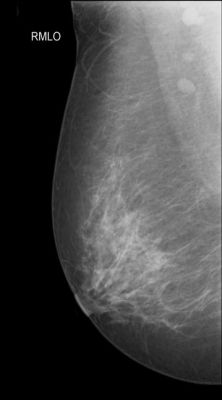

Mammography

WHAT IS DONE IN MAMMOGRAPHY?

- The breasts are compressed with compression plate and X-Rays are taken. Usually 4 X-Rays are taken

- Additional views are taken in problematic &/or doubtful cases.